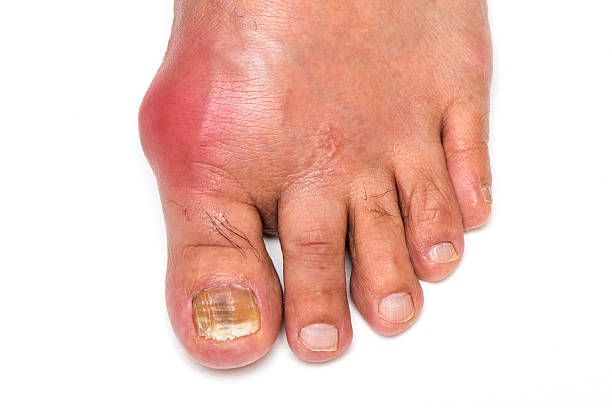

통풍 증상 두 번째는 엄지발가락 통증입니다. 처음에 주로 엄지발가락 근저부 관절에 발병하는데 돌발적인 통증과 함께 붉게 부어오르며 무릎, 손목, 발목, 팔꿈치 등에 발생하기도 합니다.

통풍 증상 세 번째는 심한 통증입니다. 무증상, 국소적인 통증에 이어 스치기만 해도 아프며 온몸에서 열이 나는데 이 때는 얇은 천이 스치기만 해도 통증을 느껴 양말을 신지 못하고 제대로 걷기 힘듭니다.

통풍 증상 네 번째는 급성 통풍 발작인데 엄지발가락, 발목 등 한 곳의 관절이 갑자기 빨갛게 부어오르고 손댈 수 없을 정도로 통증이 심한데 발뒤꿈치, 팔목, 손가락, 귀 등에서 나타나며 급성 통풍성 관절염이라고 부르기도 합니다.